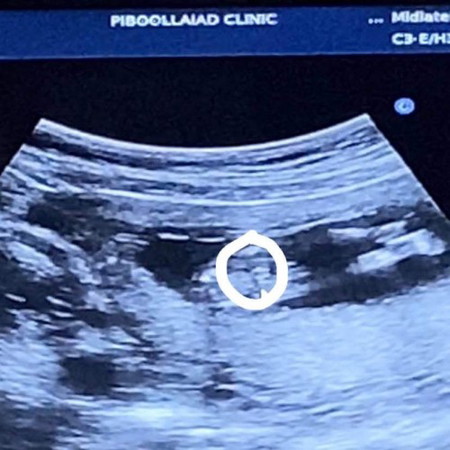

ช่วยดูหน่อยค่ะ ญหรือช คะ

หมอคิดว่าเป็น ญ แต่รอชัดกว่านี้ 13วีคค่ะ แม่ๆช่วยดูหน่อยนะคะ

ผู้หญิงจ้าแม่ เห็นเป็นกลีบๆ🥰